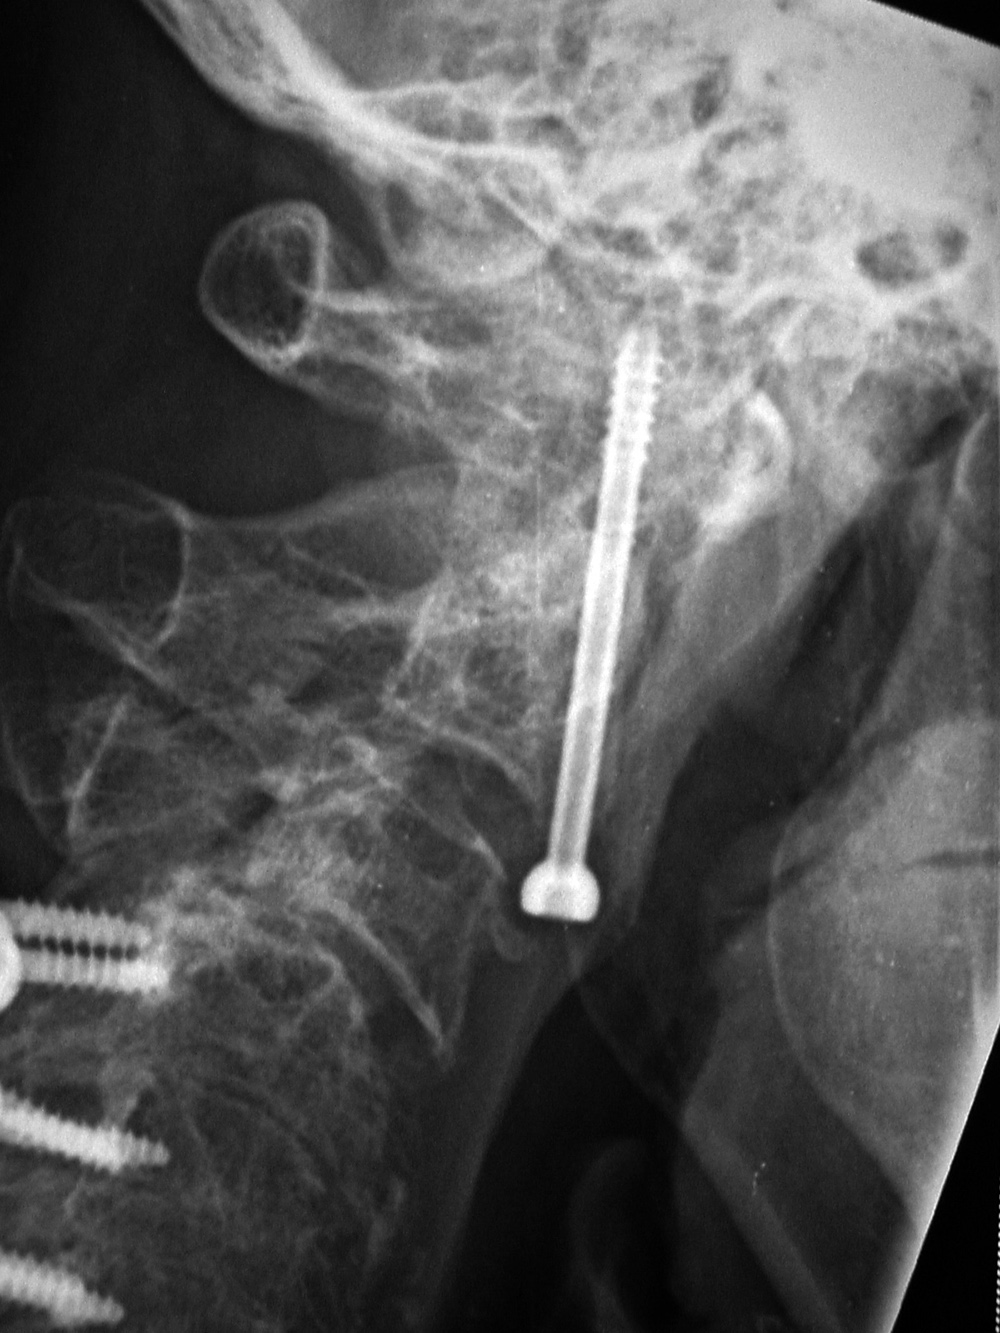

Reduction is generally required if the odontoid fracture fragment is displaced more than 4 mm anteriorly on the body of C2. Posterior cervical fixation wires are commonly used for treating type 2 odontoid fractures (figure: odontoid fracture fixation and sublaminar wiring). They usually achieve satisfactory odontoid fusion, but they may limit neck rotation. Because of this, odontoid fracture fixation may use an odontoid compression screw or nail (Esses, 1991) running caudal to cephalad through the body of C2, the odontoid fracture line, and into the body of the odontoid (figure: odontoid fracture fixation and sublaminar wiring; figure: odontoid screw). On rare occasions, two odontoid fixation screws may be used (figure: two odontoid fixation screws).

Odontoid fracture fixation may be approached either anteriorly or posteriorly (Winegar, 2019). Partially threaded lag screws are used for the anterior approach, because they produce interfragmentary compression and immediate stability. In this case the transverse ligament has to be intact to preserve anteroposterior stability. If a posterior approach is used, there is usually atlantoaxial fusion (figure: type III odontoid fracture). This considerably limits cervical spine movement eliminating normal atlantoaxial rotation and reducing cervical flexion-extension (Winegar, 2019).

Posterior cervical spinal clamp Odontoid fracture fixation

The disk cage is probably composed of PEEK.   Patient with rheumatoid arthritis and atlantoaxial (C1-C2) subluxation and generalized cervical spine laxity Postoperative lateral radiograph of the cervical spine. There is fixation of an odontoid base fracture by an odontoid screw and a sublaminar wire between C1 and C2. There are also skin staples and a surgical drain in the posterior aspect of the neck.